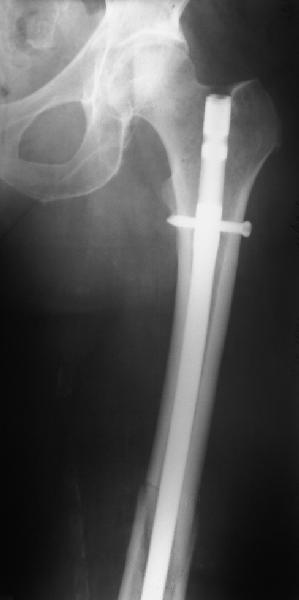

В приложении - недавний перипротезный перелом.

Методичка по закрытому интрамедулярному остеосинтезу при дистальных переломах бедра тут.